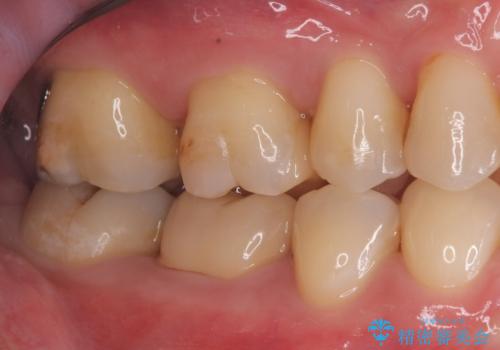

- 主訴:銀色の詰め物が取れてしまった。下の歯は笑うと見えるので、これを機に白くしたい。

保険適用のメタルインレーが脱離しており、歯冠色で審美性、適合性の良いセラミックインレーでのやり替えを提案しました。

メタルインレーが脱離した咬合面の窩洞内は、う蝕を除去し、セラミックインレーの厚みの担保とメタルタトゥー部分の除去を目的に形成を行いました。

インレーセット時はラバーダム防湿を行っています。